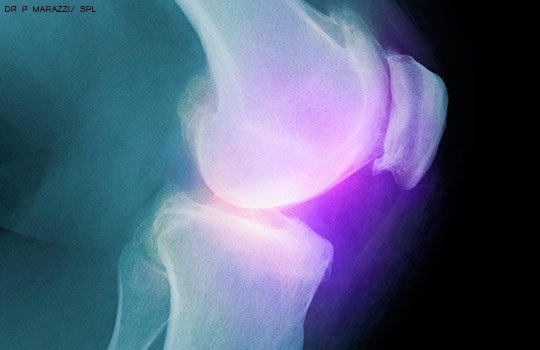

Recomiendan no hacer artroscopía en artrosis de rodilla

Una guía de práctica clínica desaconseja la cirugía artroscópica para la artritis degenerativa de la rodilla y los desgarros meniscales. BMJ, 10 de mayo de 2017